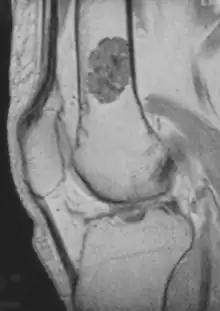

| Micrograph of an enchondroma. H&E stain. |